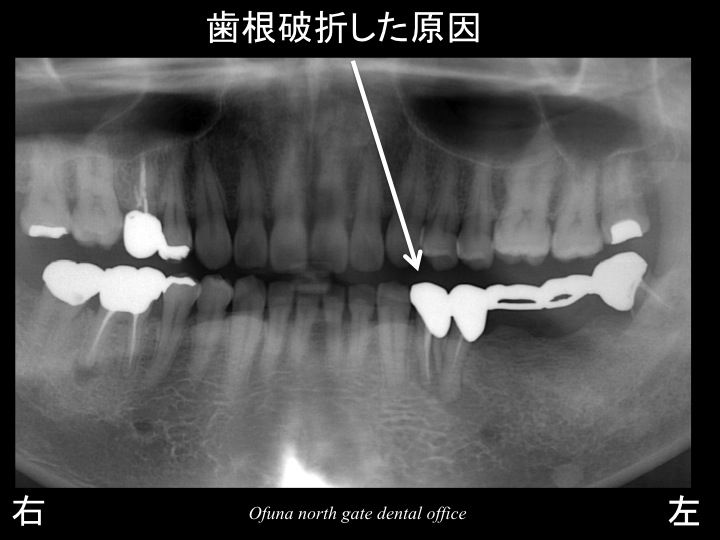

以下が初診時です。

診査の結果、問題がいっぱいありました。

一番奥歯は、虫歯が大きく進行していました。

奥から2番目は、根の先に膿みが大きく溜まっている状態でした。

奥から3番目は、歯根破折 している状態でした。

それでは、なぜこのようなことが起こったのでしょうか?

どのようなこともそうですが、まず歯がダメになった原因を考えることが必要です。

この理由として 神経がない歯が多いということです。

神経のない歯は もろく 通常の咬む力でも割れてしまうことがあります。

奥から3番目の歯が歯根破折 した大きな原因は、こうした神経がないことと、ブリッジであったことが考えられます。

進行した虫歯、

根の先に大きな膿みが溜まっている、

歯根破折 している

ということから

以下の×印は将来性が低いため、抜歯と判断しました。